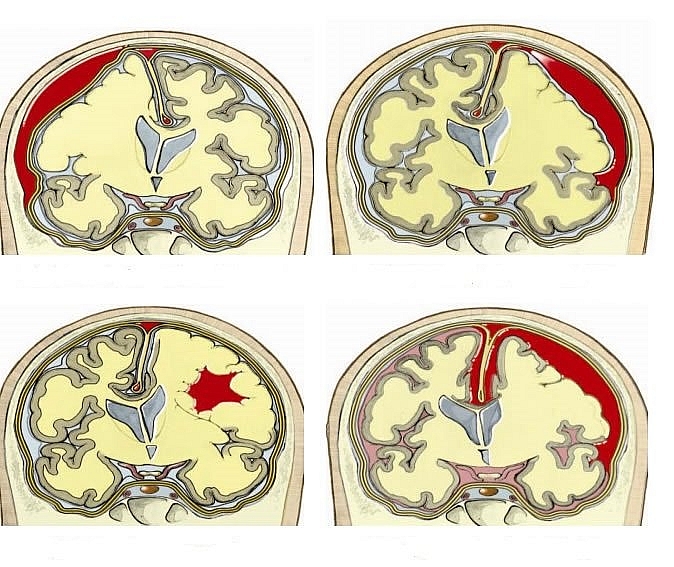

Chấn thương sọ não là tình trạng bệnh nhân bị sang chấn vào đầu gây tổn thương hộp sọ và các cấu tạo khác bên trong hộp sọ. Đây là một dạng chấn thương não mắc phải, xảy ra khi có một chấn thương đột ngột gây tổn thương não. Chấn thương sọ não có thể xảy ra khi đầu va chạm mạnh và đột ngột với một vật thể nào đó hoặc khi có một vật thể xuyên qua hộp sọ và đi vào mô não.

Các triệu chứng của chấn thương sọ não có thể nhẹ, trung bình hoặc nặng, tùy thuộc vào mức độ tổn thương của não. Một người bị chấn thương sọ não nhẹ có thể vẫn tỉnh táo hoặc có thể mất ý thức trong vài giây hoặc vài phút. Chấn thương sọ não nghiêm trọng hơn có thể dẫn đến bầm tím, rách các mô, chảy máu và các tổn thương thực thể khác cho não. Những chấn thương này có thể dẫn đến các biến chứng lâu dài hoặc gây tử vong.